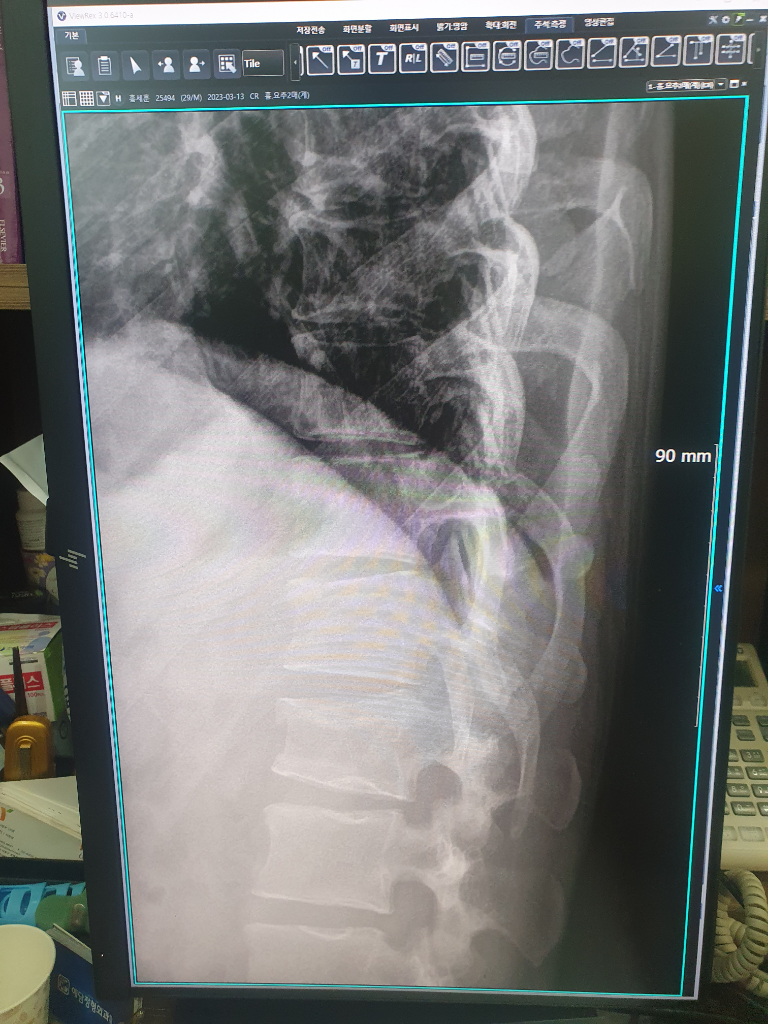

명확하지는 않지만 엑스레이로 보면 갈비뼈가 없어지는 요추 1번 정도에 골절이 있는 상황으로 보입니다.